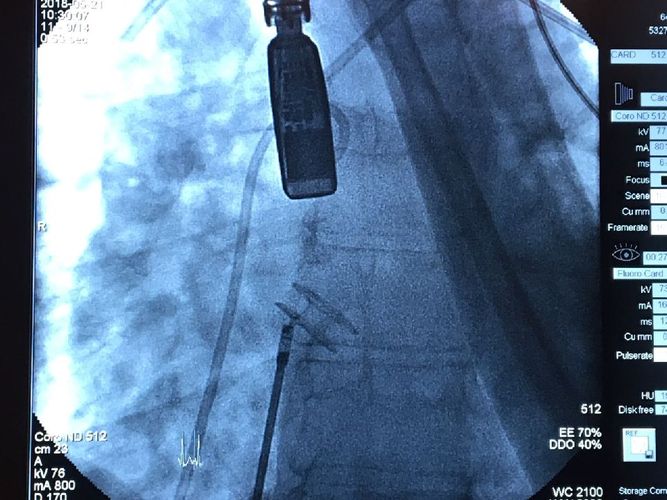

Pierwszy w Polsce kardiologiczny zabieg interwencyjny – implantacja zestawu do regulacji przepływu na poziomie przedsionków (AFR–atrial flow regulator) odbył się 21 maja 2018 r. w Uniwersyteckim Centrum Klinicznym. To wynik współpracy pomiędzy Kliniką Kardiologii Dziecięcej i Wad Wrodzonych Serca GUMed a Klinicznym Centrum Kardiologicznym Uniwersyteckiego Centrum Klinicznego (UCK). Zabieg przeprowadzono u 28-letniego pacjenta, u którego we wczesnym dzieciństwie wykonano zabieg korekcji złożonej wrodzonej wady serca i u którego rozwinęło się ciężkie nadciśnienie płucne. Za kwalifikację do zabiegu odpowiadała dr hab. Alicja Dąbrowska-Kugacka, która wykonywała przezprzełykowe badanie echokardiograficzne w trakcie zabiegu. Badanie poprzedzone zostało pomiarami hemodynamicznymi (dr Grzegorz Żuk). Zabieg został przeprowadzony przez dr. hab. Roberta Sabiniewicza, prof. nadzw. GUMed oraz dr. Dariusza Ciećwierza. W zabiegu brali również udział dr hab. Joanna Kwiatkowska i dr hab. Marcin Fijałkowski, prof. nadzw. GUMed. Nad znieczuleniem podczas zabiegu czuwał prof. Radosław Owczuk.

Implant zbudowany z nitinolowej plecionki umieszczany jest w przegrodzie międzyprzedsionkowej w miejscu wytworzonego wcześniej otworu. Celem zabiegu jest wytworzenie przecieku międzyprzedsionkowego i odbarczenie prawego przedsionka u pacjentów ze skrajną postacią nadciśnienia płucnego. Pierwsze tego typu urządzenie zostało wszczepione w USA w 2015 r. Implant znajduje się obecnie w fazie badań przedklinicznych. Pojedyncze jak do tej pory zabiegi na świecie wykonywano w wyjątkowych sytuacjach u pacjentów, u których wykorzystano wszelkie możliwości farmakologicznego leczenia nadciśnienia płucnego.